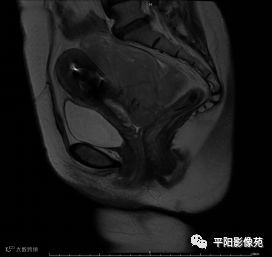

MRI表现

T2轴位

(宫腔内见金属节育环伪影)宫颈区见不规则形等T1稍长T2信号软组织肿块,DWI序列呈明显高信号,大小约为3.87cmX2.64cm,双侧宫颈基质低信号环连续性中断,病灶向子宫右后上方生长,周围脂肪间隙模糊,增强扫描明显强化,强化程度低于子宫及宫颈实质;子宫后方、子宫直肠间隙见不规则形长T1长T2信号软组织肿块,DWI序列呈高信号,大小约10.12cmX4.82cmX10.29cm,病灶呈分叶状,向下方生长与宫颈分界不清,与直肠分界尚清,增强扫描明显不均匀强化。